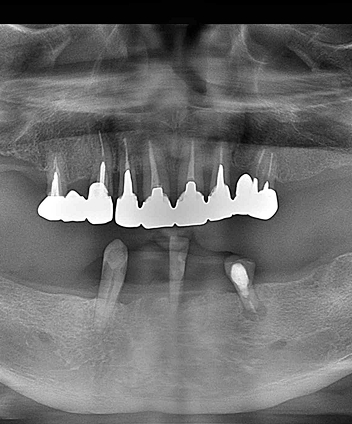

All-on-4は、少ない本数のインプラントで多数の歯を支えることができる、

画期的な全顎再生治療です。

手術の負担が少なく、骨の量が足りない方でも対応できる可能性が高いため、

これまでインプラントを諦めていた方にも新しい希望をもたらします。